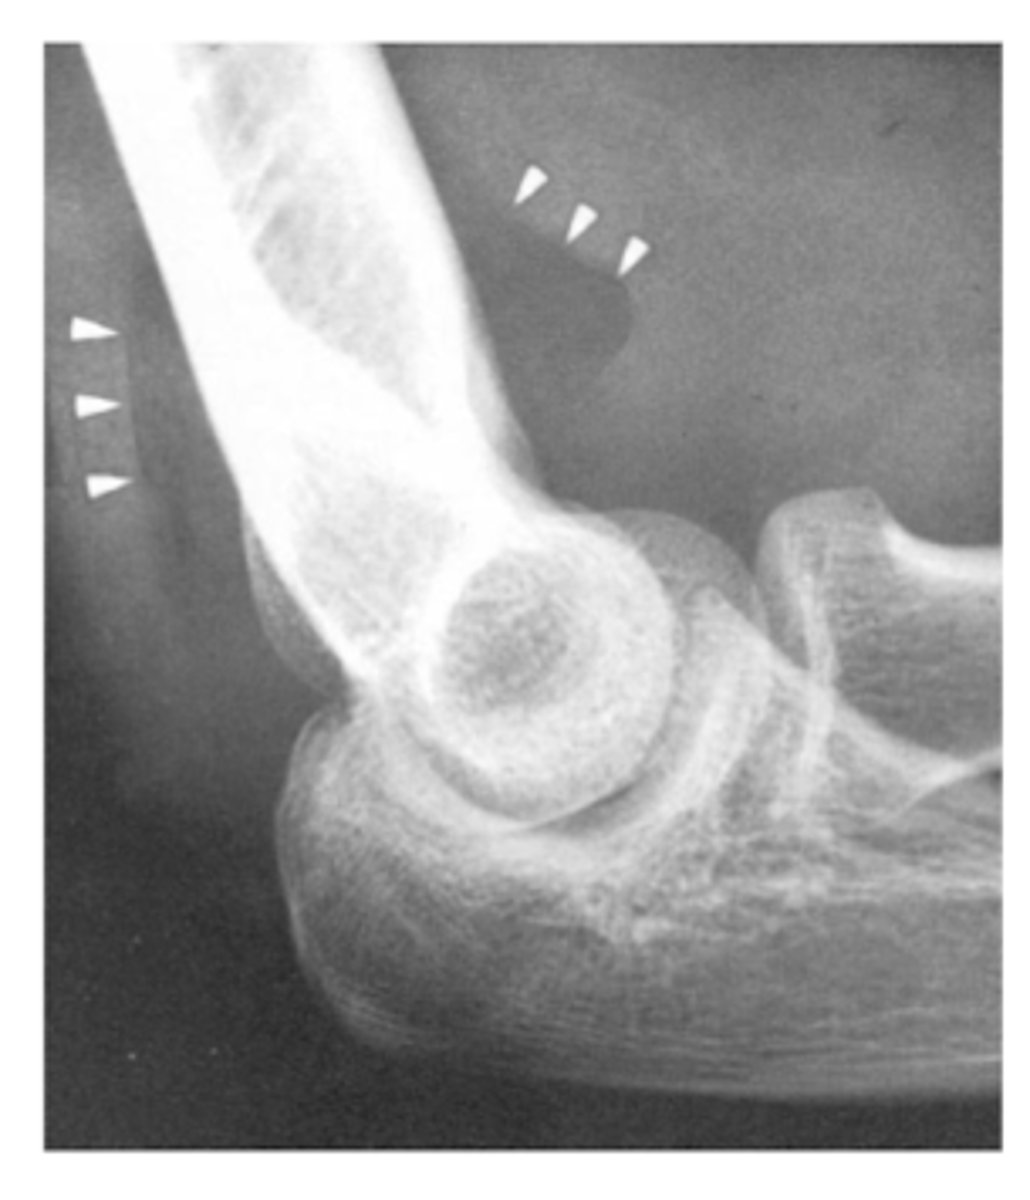

What does a fat pad sign/sail sign on elbow XR suggest? What type most common in adults and children?

presence an articular hemorrhage due to an occult or intra-articular fracture

Adults → radial head Fx

Children → supracondylar Fx of humerus